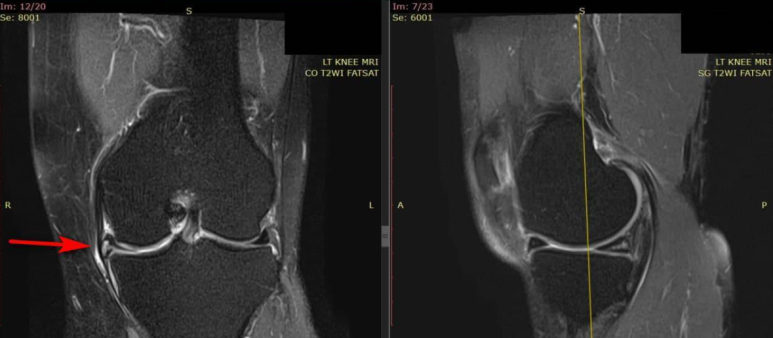

MRI 영상 판독소견서를 보니

내측 반월판 후각의 오래된 만성 파열(MMPH Chronic tear)로 진단되었습니다.

가져오신 MRI 영상의 내측 반월상 연골 파열

가져오신 MRI 영상과

음곡혈 초음파를 비교해보니

내측 반월상 연골 파열(빨간 화살표)과

파열 부위와 연결된 반월판 낭종(노란 화살표)이

보입니다.